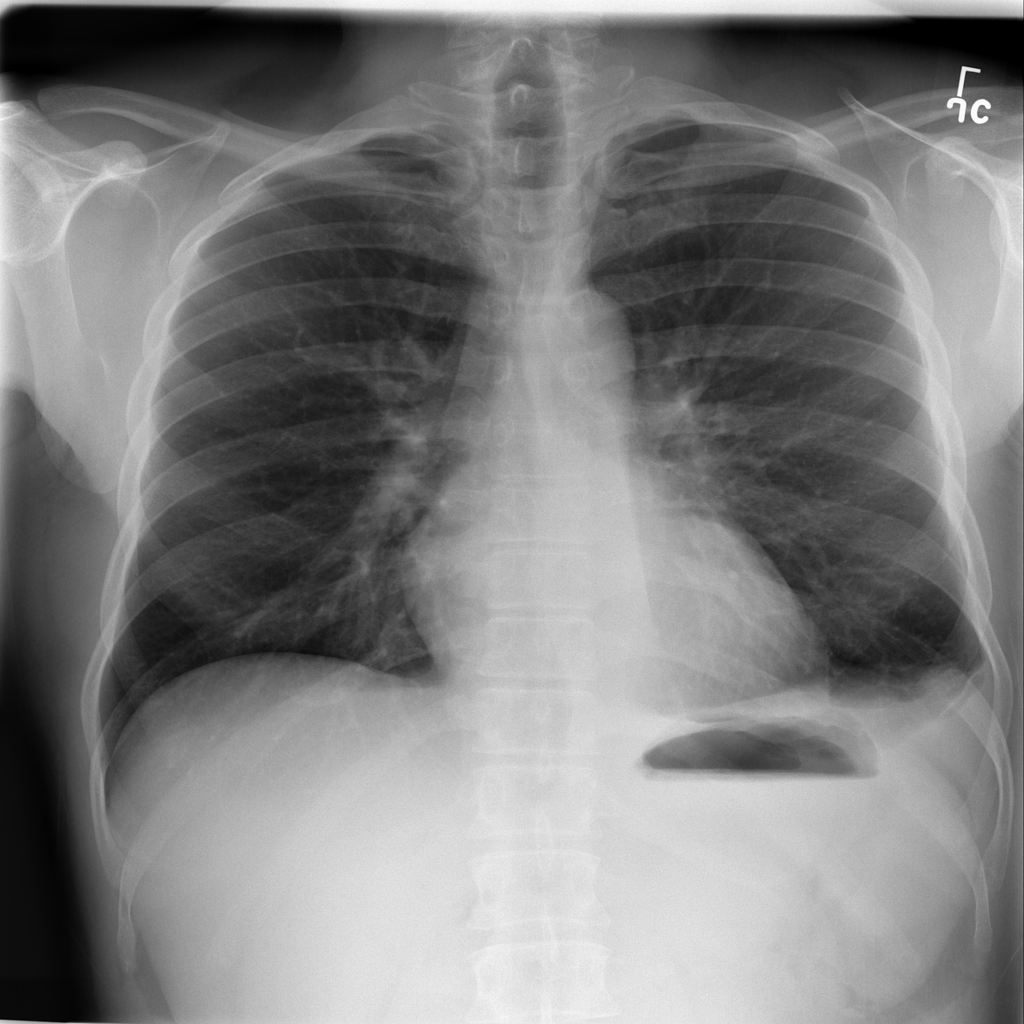

PAT-1F50 · IMG-000Fibrosis

PAT-1F50 · IMG-000

PA